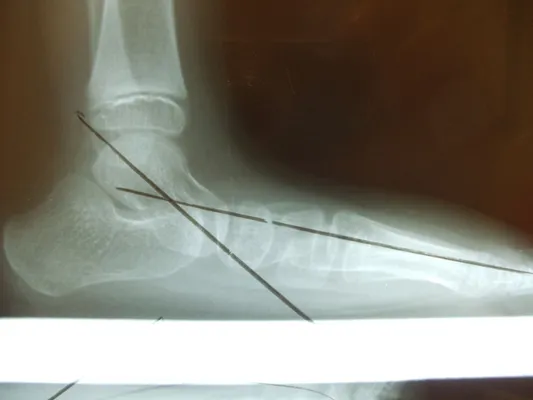

Pre-operative x-rays of the flatfoot with the talus deviated medially due to subluxing off the calcaneus causing the midtarsal joint to sublux laterally and uncovering of the talar head at the talo-navicular joint (left). The talus bone should line up with or be close to paralletl with a line drawn through the 1st metatarsal shaft (right). This is referred to as Meary's angle.

One case see an improvement in Meary's angle after surgical repair of the flatfoot with a subtalar joint implant which blocks the subluxation of the talus off of the calcaneus.